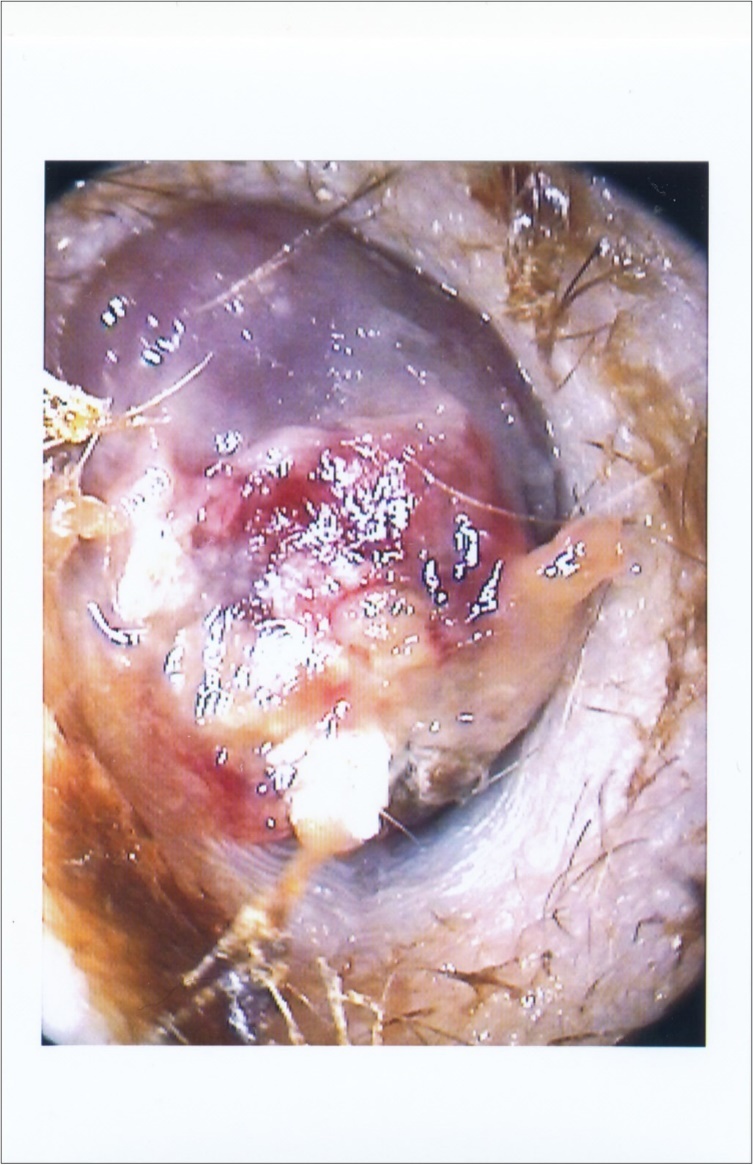

when the facial nerve paralysis started, it was House-Brackmann grade V/VI. The external canal was fully occluded with reddish-purple soft mass with bleeding on touch. (Figure 1). There was no redness or narrowing in external canal skin. No lymph nodes detected. Her nasal and throat examination was clear. The rest of neurological examination was normal. She didn’t have any weight loss nor night symptoms of increase temperature or sweat. The audiogram showed conductive hearing loss with air-bone gap 20 dB at 1000 Hz.

Figure 1.Right ear shows reddish-purple mass